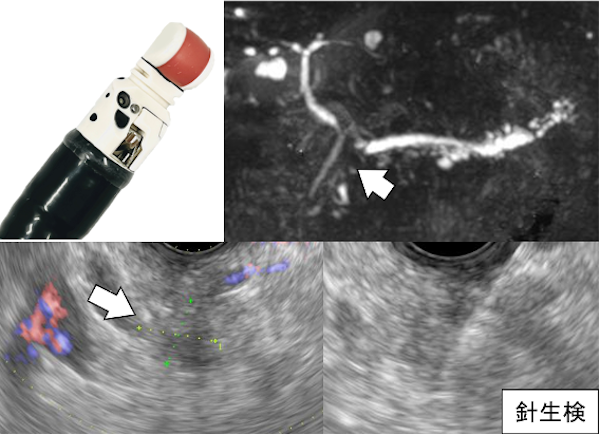

胃や腸から膵臓・胆管にエコーを当てて、「がん(矢印)」などの病気がないか検査します。必要に応じて超音波内視鏡下に「針生検」も行います。

・胆管閉塞に対する超音波内視鏡下治療

がん等で十二指腸が狭くなった場合、超音波内視鏡を使用し、胃などから胆管内に「プラスチック・金属のチューブ」を留置します。

・胆のう炎への治療

胆のう炎に対し外科手術が行えない場合は、体の「外側」・または「内側(内視鏡で腸内から)」からチューブ(矢印)を入れ、胆のう内の膿を除去します。

・重症膵炎に対する内視鏡治療(壊死物質除去)

重症膵炎などにより、お腹に壊死物質が溜まってしまった場合、超音波内視鏡で胃などに金属の管を入れ壊死物質(矢印)を除去します。